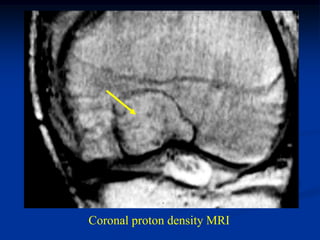

Case #572

15 year female

Ollier’s disease

AP close up knee